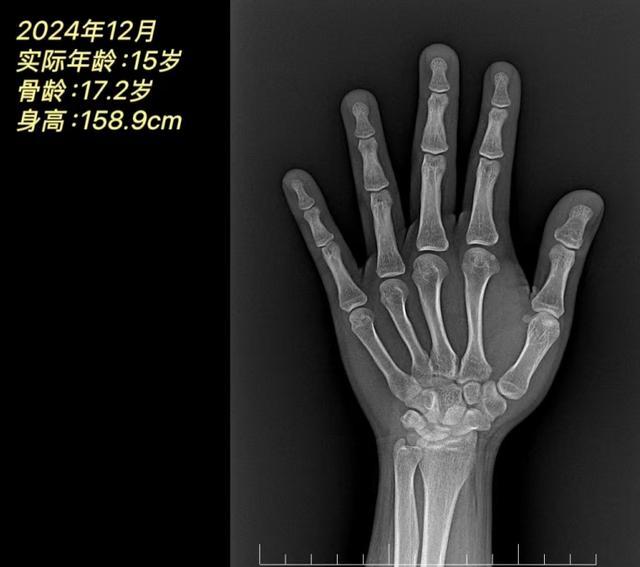

在谭主任细细询问后了解到,奇奇爸爸的身高有168cm,妈妈的身高有155cm,奇奇的遗传身高应该在168±5cm。但是根据后来开具的一系列检查结果显示,奇奇目前的身高仅有158.9cm,体重却高达77.5kg(>P97),骨龄为17.2岁,超过实际年龄2.2岁,最终诊断为:“肥胖、脂肪肝”。并且非常遗憾的是骨龄已经提示是“闭合状态”,这也就意味着奇奇再无长高机会!